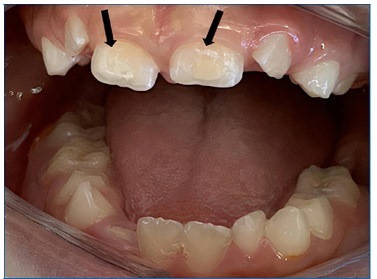

Intraoral examination revealed the presence of gingival hyperplasia in the upper arch and gingivitis associated with the presence of dental biofilm, arched palate, Angle class I occlusion without crossbite or open bite, dolichofacial pattern, labial hypotonia, and mild enamel hypomineralization (presence of whitish-cream demarcated opacities)14 in the permanent maxillary central incisors (Figures 4 and 5). Moreover, she had caries lesions in the deciduous mandibular left second molar and mandibular first permanent molar, which presented great coronary destruction and pulp involvement (Figures 6 and 7).

Figure 4 Gingival hyperplasia in the upper arch and gingivitis associated with the presence of dental biofilm, arched palate